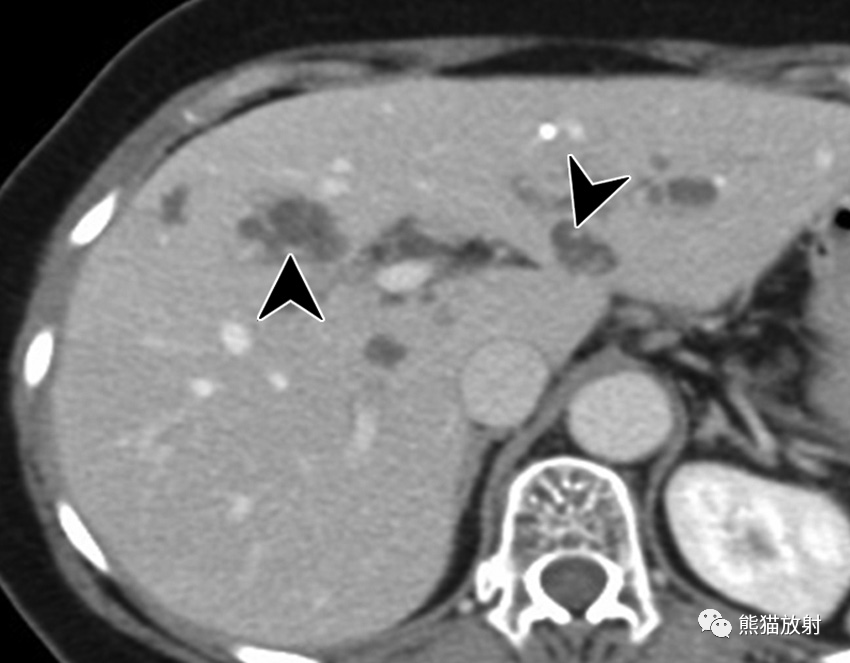

24岁男性,HIV感染患者,盗汗、发热,播散性结核感染。对比增强CT显示肝脏(黑箭)和脾(箭头)实质内多发微小低密度病变,腹膜后多发增大淋巴结(白箭)。

6岁男孩,肝巴尔通体病,被猫抓伤后发热3周。轴位增强CT图像显示多个低密度肝结节(箭)及门静脉周围增大淋巴结(箭头)。这些病变与转移瘤鉴别困难。然而,在无已知恶性肿瘤的免疫功能正常的年轻患者中观察到多发性肝脏病变应考虑到有肝巴尔通体病的可能。

巴尔通体病(猫抓病)是由巴尔通体引起的感染,该革兰氏阴性菌通过猫抓或咬伤引入人类宿主,最常影响儿童和年轻成人。猫抓或咬伤后1-3周开始出现症状,受伤部位近端出现疼痛性淋巴结肿大和发热。在无淋巴结肿大的情况下可发生内脏受累,表现为不明原因的发热。巴尔通体病的诊断可通过血清学试验、PCR试验或活检证实。播散性感染见于5%-10%的病例 。肝巴尔通体病的特征是多发性坏死性肉芽肿,范围为3-30mm,伴或不伴肝肿大。